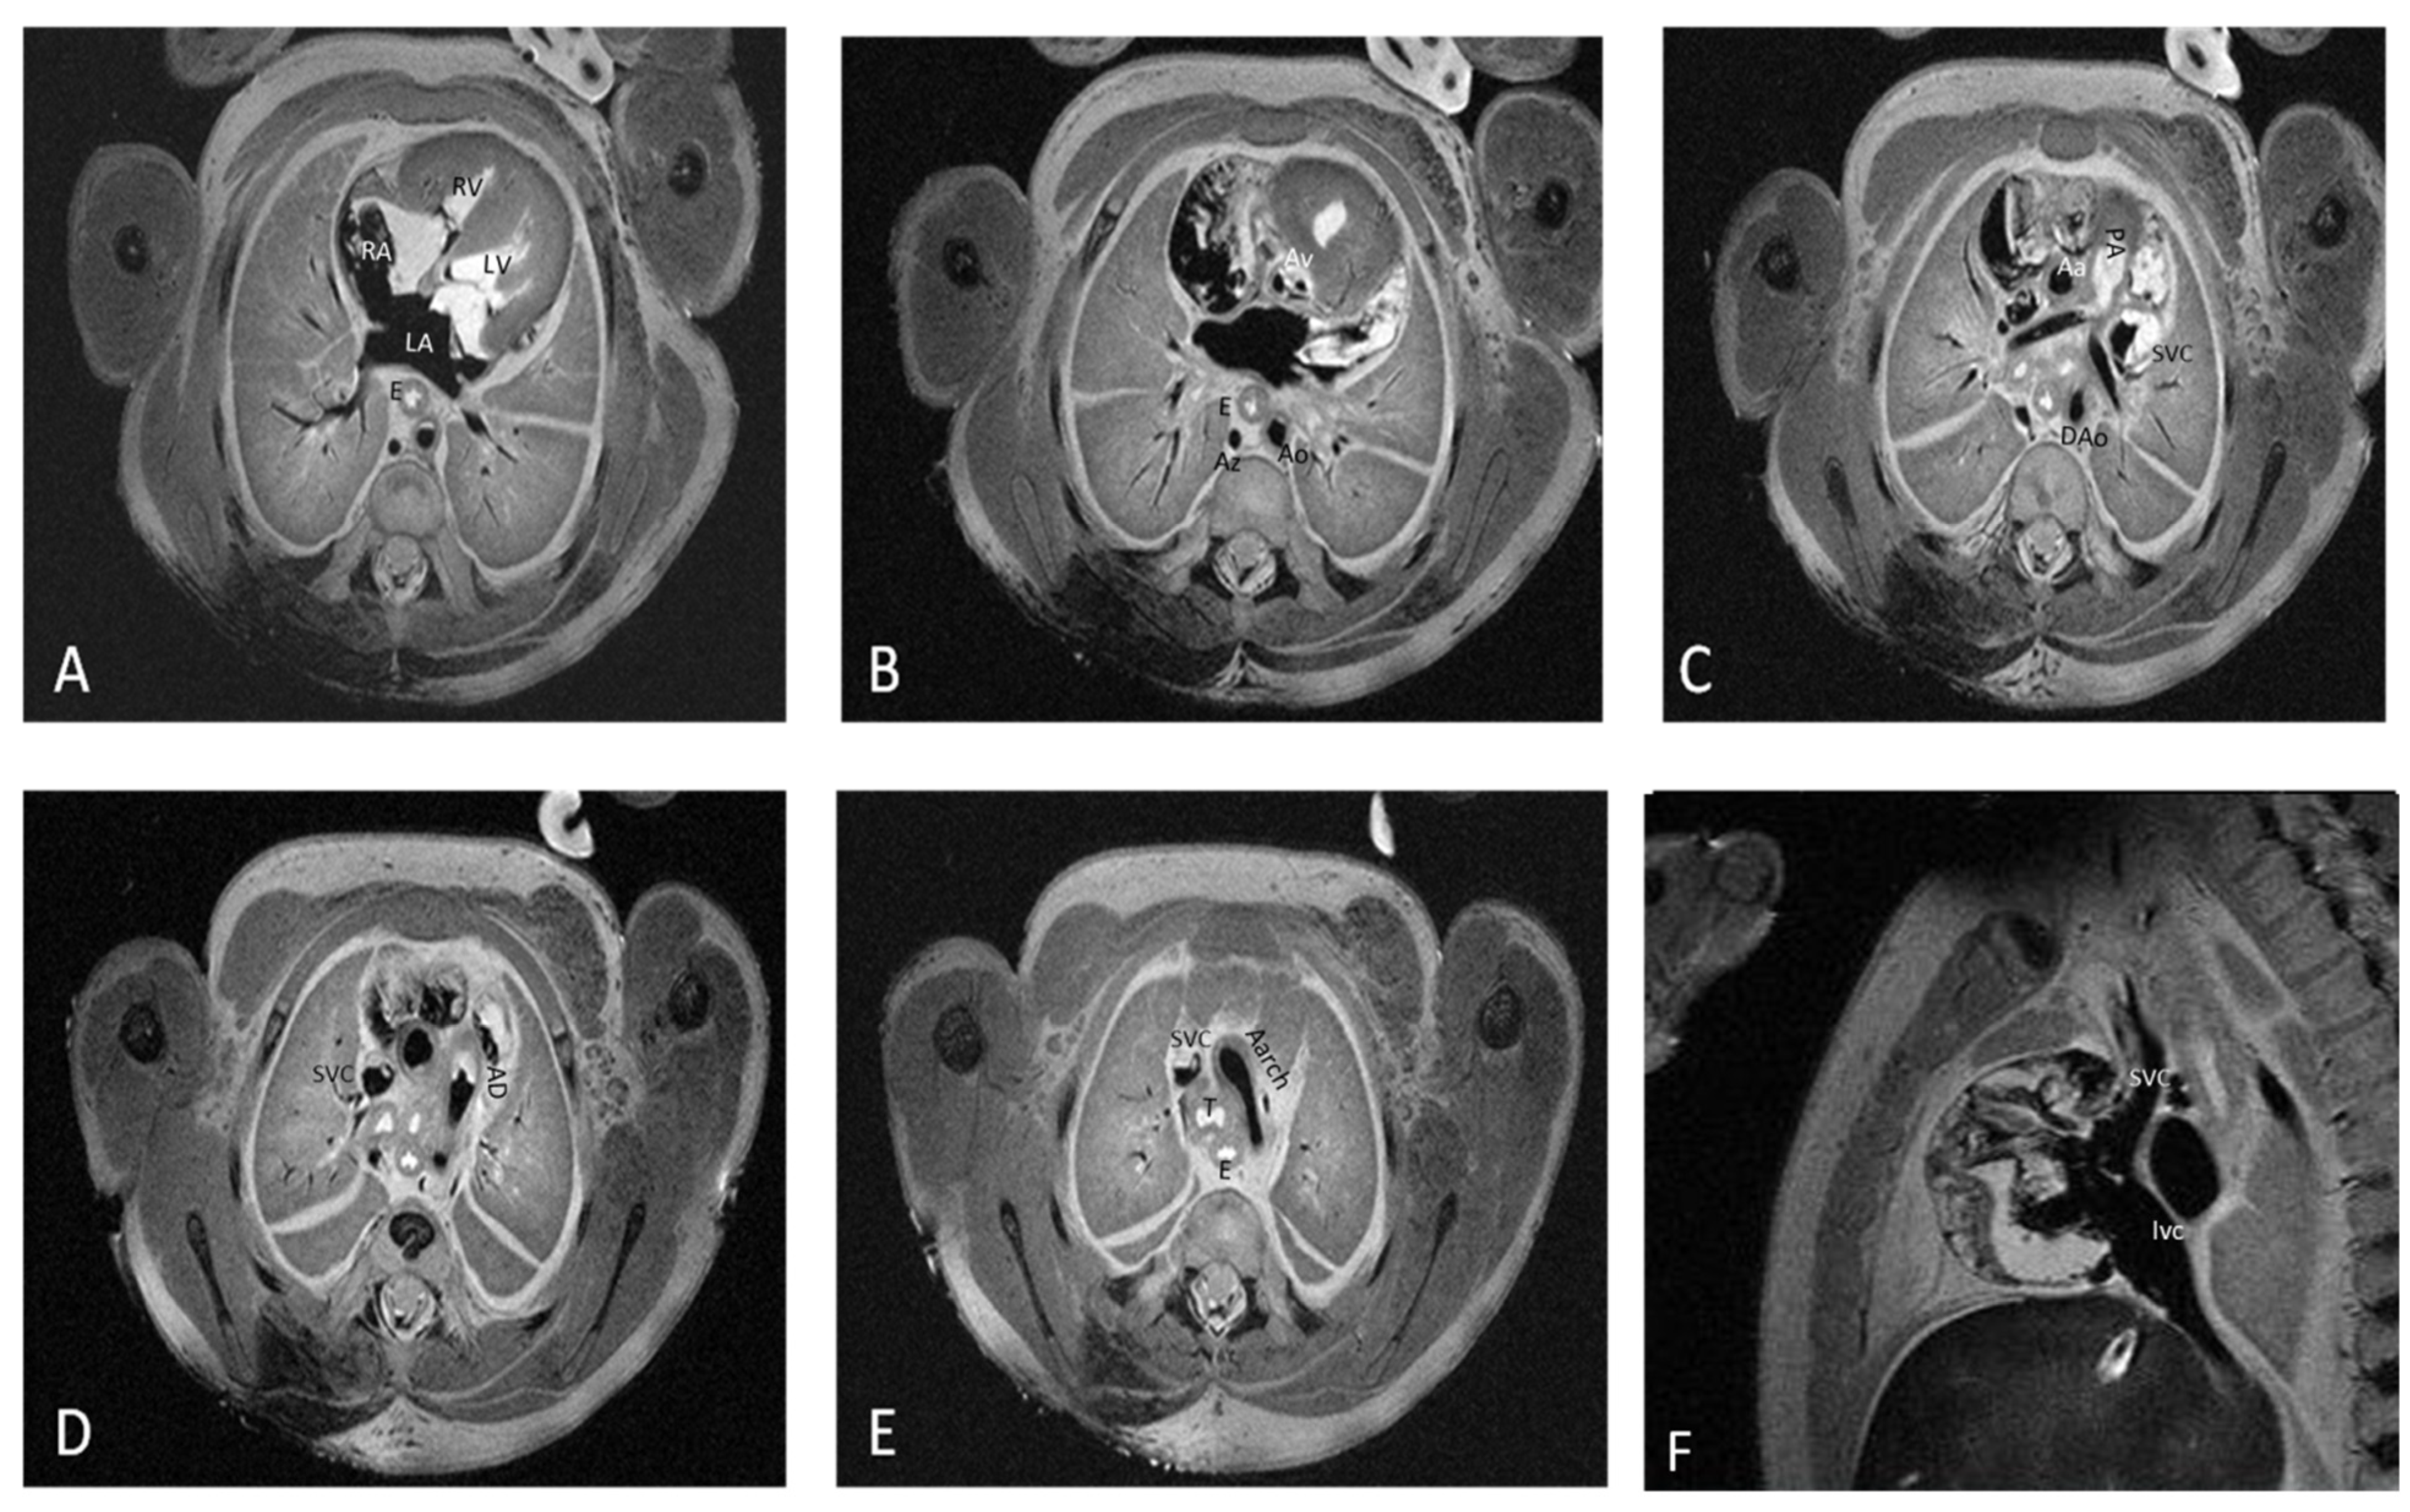

The post-mortem fetal imaging scan at 7T required a medium time of 2 h and 30 min. The images were acquired in axial, sagittal, and coronal sections for 3 regions: the head and neck, thorax and abdomen, and pelvis. A 1H volume coil with an inner diameter of 60 mm was used. Details regarding fetuses’ positioning and the pilot protocol used for pm-MRI at 7T were described in previous research [

15]. The sequence parameters are listed in

2.3. Image Analysis

All images were analyzed by one radiologist with expertise in fetal and pediatric examination and by one embryologist with experience in embryo and fetal imaging blinded to the prenatal ultrasound results. The images were processed with the GE AW Workstation 4.6 (GE Healthcare, Chicago, IL, USA). Each specialist analyzed all images separately and the final diagnosis was approved by both specialists. The agreement index was not considered due to the different specialties of the imaging evaluators.

According to Anderson and Shirali [

3] in the sequential segmental analysis of the heart, for each case, the atrial, ventricular, and arterial segments and their connections; the atrioventricular valves; and the great vessels’ semilunar valves were assessed.

Fourteen distinct anatomical structures were evaluated by both examination methods: caval veins, pulmonary veins, the right atrium, the left atrium, the interatrial septum, the tricuspid valve, the mitral valve, the right ventricle, the left ventricle, the interventricular septum, the infundibulum, the pulmonary artery, the aorta, and the arterial duct.

For each structure, the imagists examined normal or abnormal morphological aspects and mentioned the observed abnormal morphological aspects.

Figure 1 depicts the fourteen cardiac items evaluated.